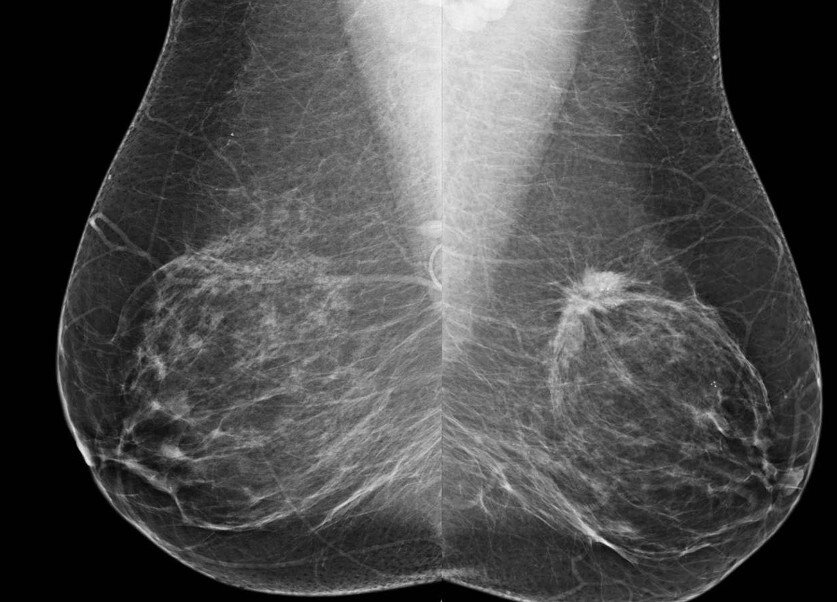

Маммография — это неинвазивный способ обследования новообразований в тканях молочной железы. При маммографии можно выявить образования, которые при пальпации не определяются, а также дать предварительную оценку потенциала образования, включая микрокальцинаты.

Процесс диагностики молочных желез заключается в компрессии органа в двух проекциях и визуализации ткани на рентгеновских снимках.

Маммограф позволяет получать снимки молочных желёз высокой контрастности и четкости тканей, что делает диагностику ещё более точной. Кроме того, цифровая ММГ позволяет многократно увеличивать изображение с отдельными участками молочной железы. Точность исследования – 95%.